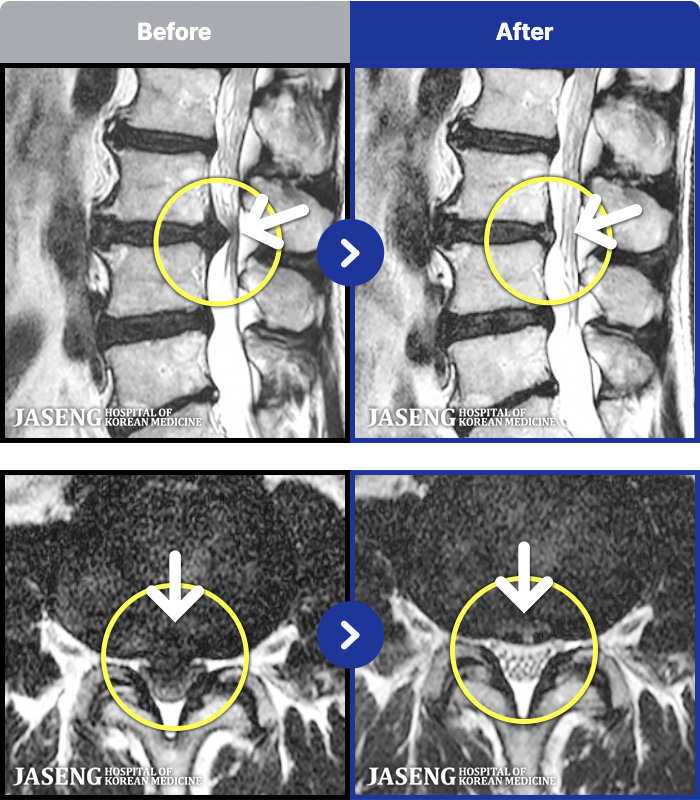

1,287 MRI ũ ʸ Ȯϼ.